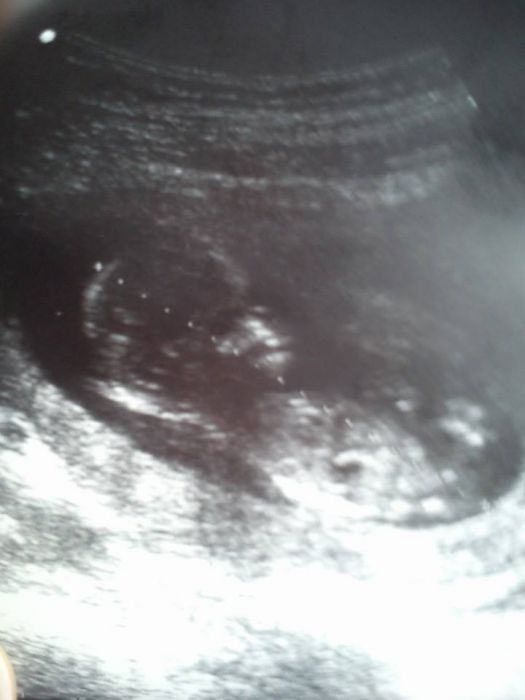

tak jsme po prvním velkém ultrazvuku a ulevilo se mi protože mi paní doktorka řekla že je miminko zdravé a že je už 14tt takže předtím nejspíše bylo špatně vidět že si doktor myslel že je menší.. Nemužu se dočkat až ho zase uvidím přikládám foto abych se s vámi podělila o své štěstí...